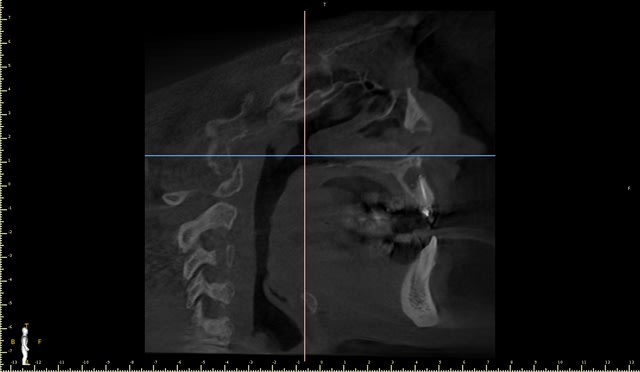

J ai obture a l hydroxyde de calcium avant de reobturer .

Pas d evolution en un an .les scans sont au cab .la lesion est tjs identique .

L'endo est belle, la resection apicale a toute les chances de marcher. Et puis au pire je ne vois pas pourquoi ne pas tenter !

Mais SURTOUT pas de comblement ni membrane, on est sur une cavité, pas sur une ROG, ça va se remplir de sang et le périoste fera membrane.